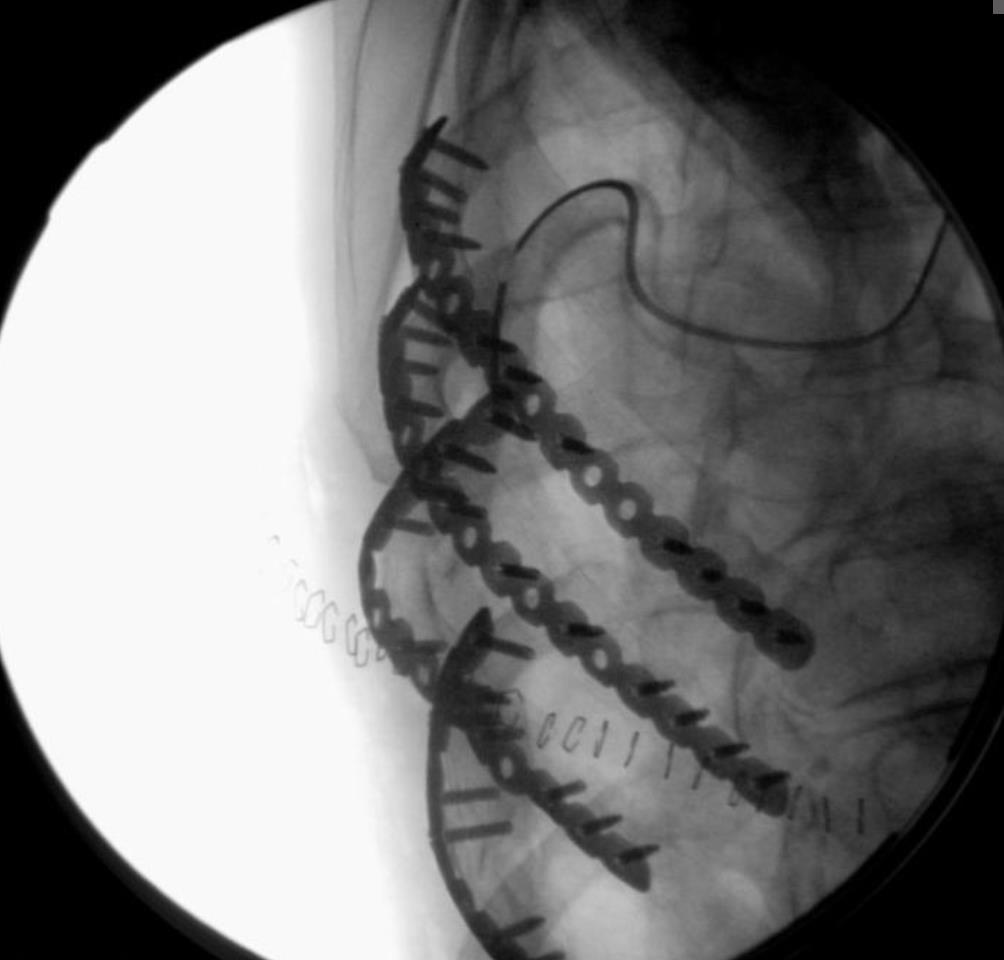

STRACOS™ Strasbourg Costale Osteosynthese System

• The STRACOS (Strasbourg Costale Osteosynthese) System is a titanium chest wall fixation platform that uses malleable rib and sternal clips, rather than plates and screws, to stabilize rib fractures, flail segments, and sternal injuries.

• According to manufacturer information, the 3D rib clips and sternal clips are preassembled and can be bent and twisted in three dimensions to conform to individual rib and sternal anatomy, providing functionally stable but non-rigid osteosynthesis.

• The screwless construct is intended to preserve physiologic chest wall motion while minimizing damage to the intercostal neurovascular bundle.

• Titanium 3D rib clips with 6, 9, or 13 segments in standard and XL widths for transverse, oblique, and comminuted rib fractures, plus straight rib clips and serrated connecting bars for bridging segmental defects.

• Screwless fixation with three-dimensionally formable clips designed to provide functionally stable, flexible osteosynthesis rather than rigid plating; only one universal rib fixation plier is needed for all rib clips.

• STRACOS uses pre-assembled titanium 3D rib clips and sternal clips that can be shaped three-dimensionally by axial torquing and horizontal bending to match the patient anatomy.

• According to the manufacturer, this design provides functionally stable, flexible osteosynthesis rather than rigid plating and reduces intraoperative configuration time because each clip is a single integrated implant.